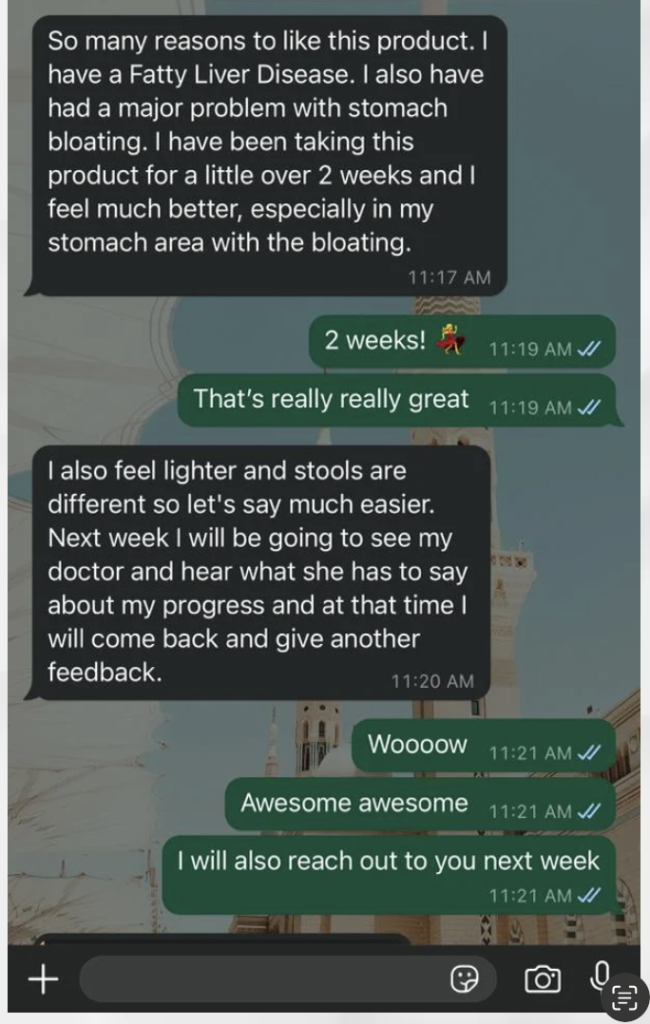

Proof that it works! Here are the few words of men that Our Liver & Hepatitis has greatly helped |

Alot of people are using this LiverDefense already to reverse fatty liver and hepatitis:

But don't just take our word for it. Here's what our raving clients are saying